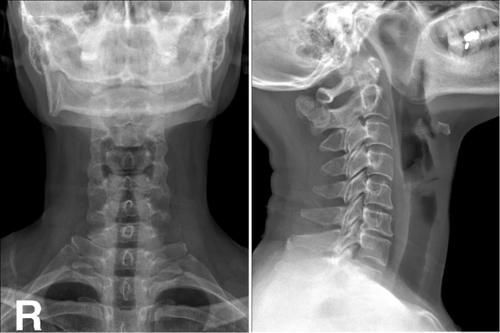

Case4:F,34y;第2、3颈椎棘突骨软骨瘤。

文章插图